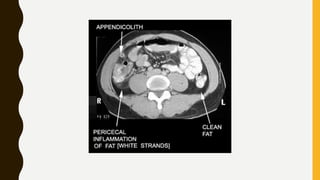

CT IN APPENDICITIS

• In past clinical diagnosis of appendicitis obviated any need for imaging,

but with proven accuracy of available imaging modalities has become

increasingly popular to reduce negative appendicectomy rates.

• In children , pregnant female ultrasound is the best, to avoid radiation

exposure.

• Retrocecal appendicitis can readily escape detection with ultrasound.

Hence CT is the next modality of choice in most adults.

• The diagnosis of appendicitis in CT requires identification of thickened

appendix (>7mm), with peri appendiceal inflammatory changes. Other

sign may include free fluid, thickening caecal pole

• Both CT and ultrasound can also identify collections if an inflamed

appendix ruptures.